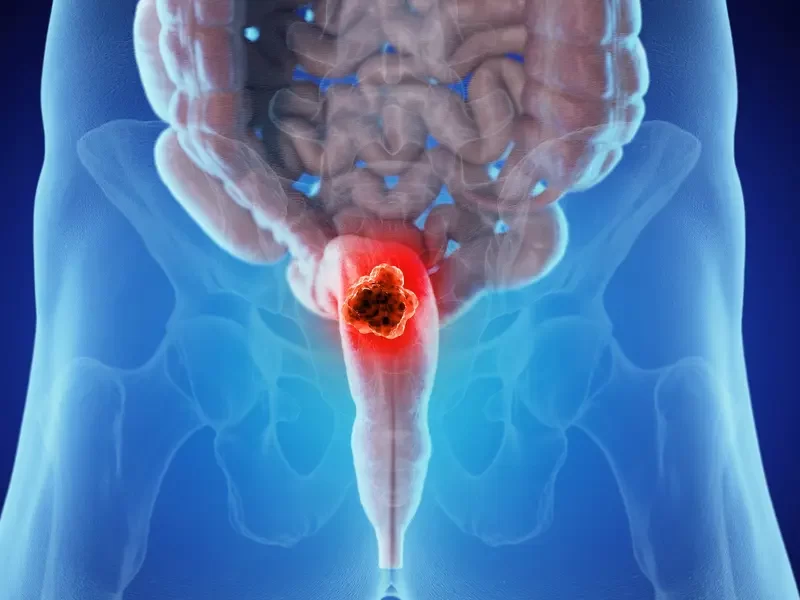

Innovative Oncology Services

Our Services

Oncology Services